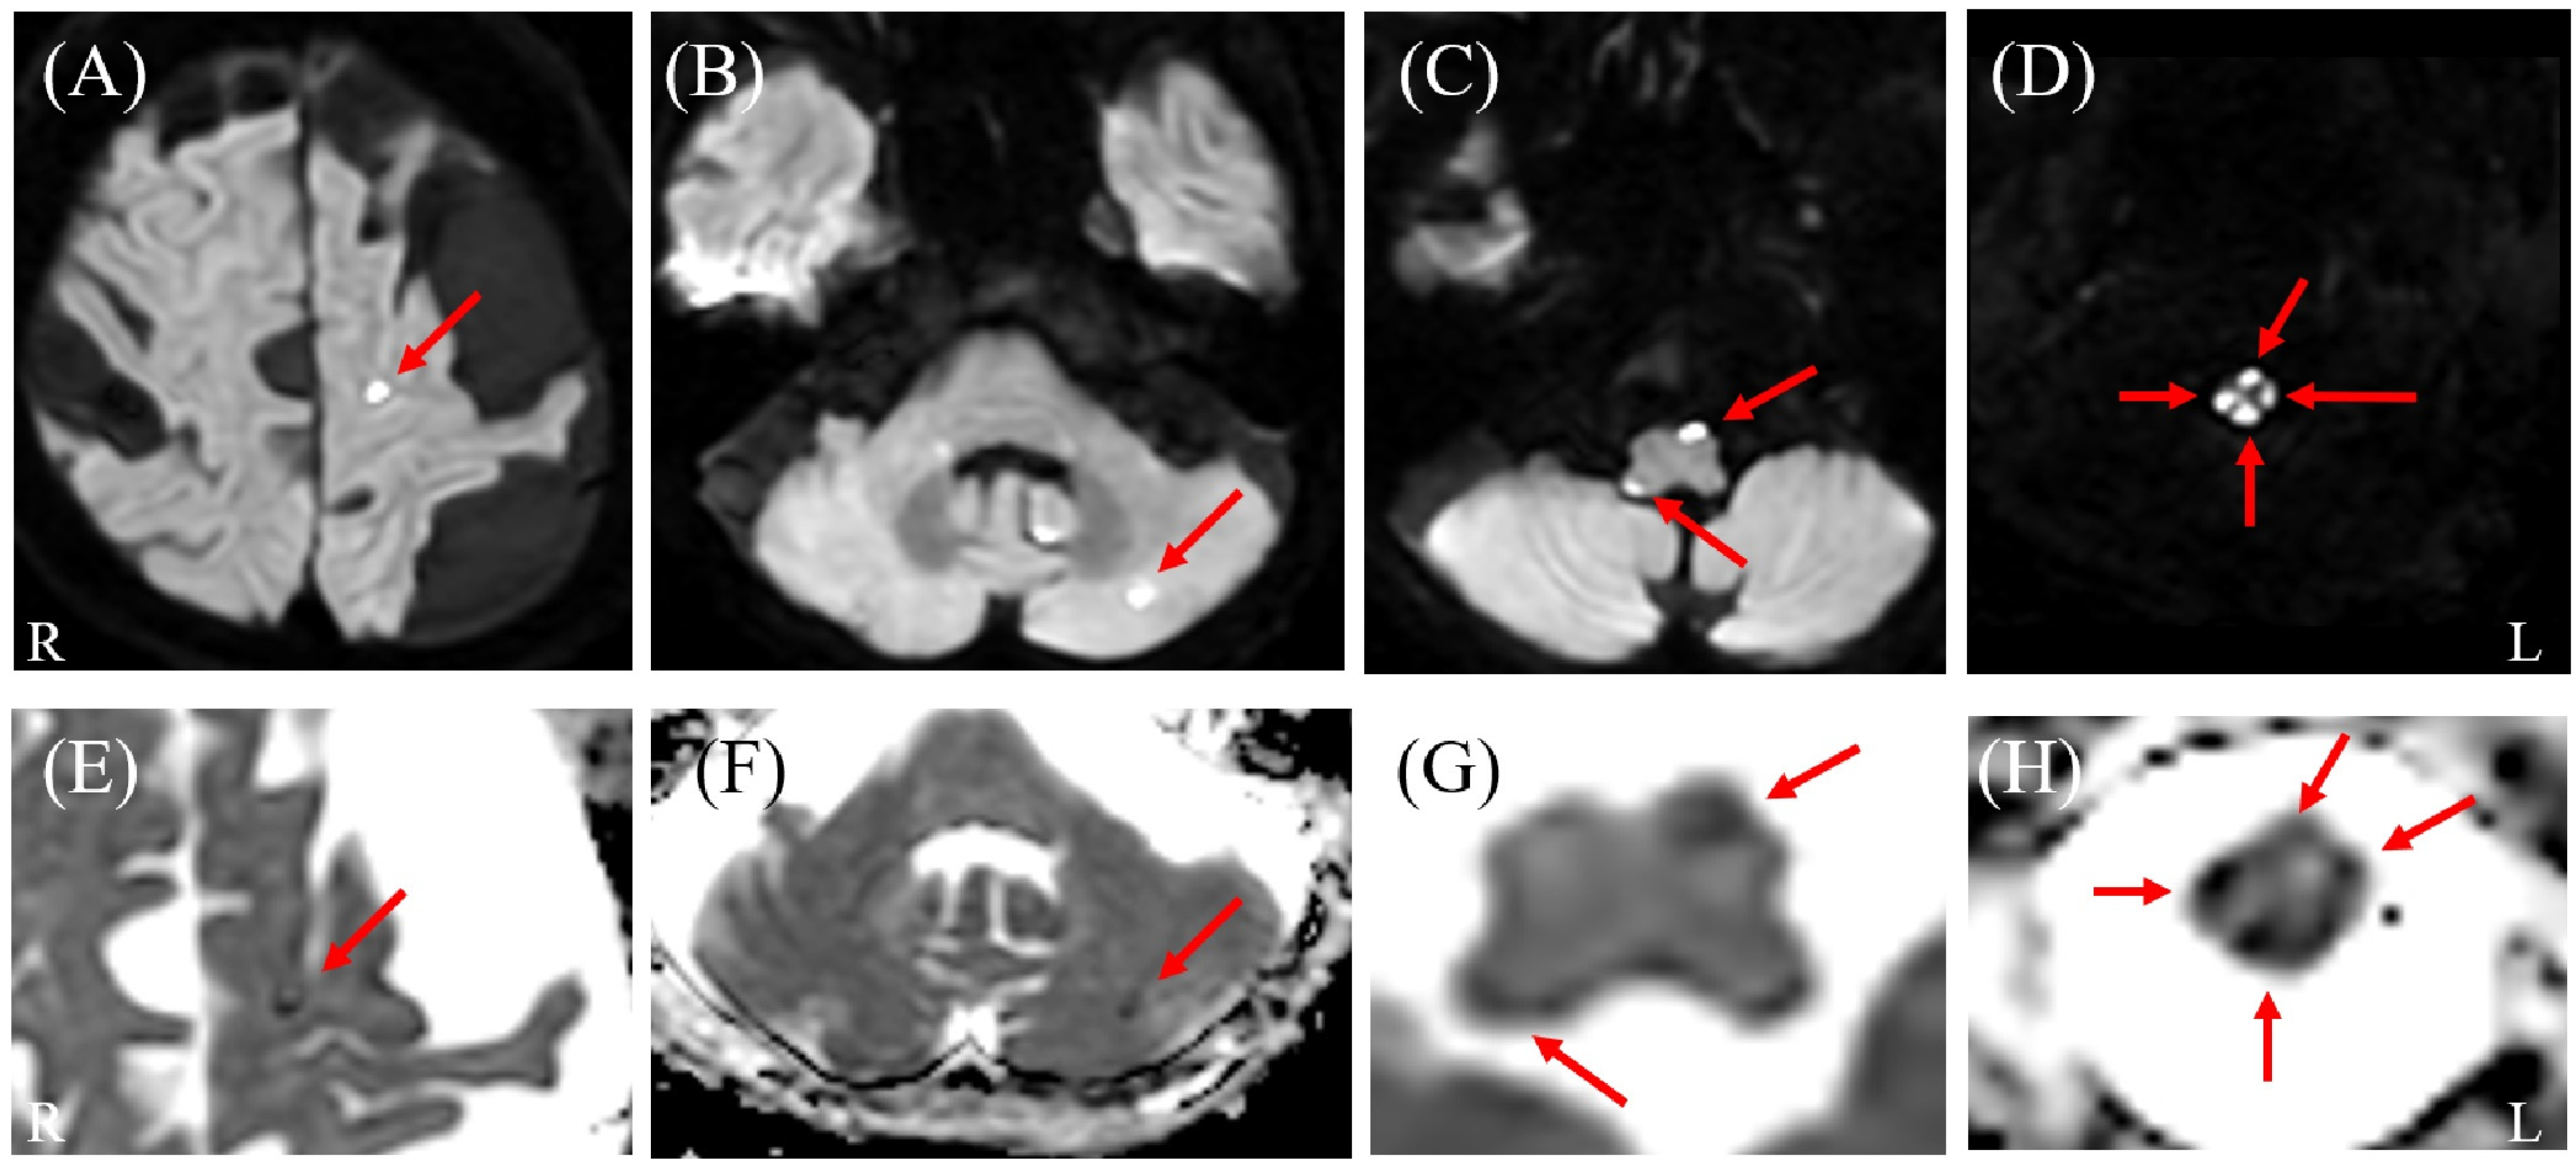

Brain magnetic resonance imaging (MRI) results. Diffusion-weighted imaging (DWI) (A–D) and corresponding apparent diffusion coefficient (ADC) maps (E–H) reveal multiple scattered lesions with diffusion restriction in the cerebral hemispheres, cerebellum, and brainstem (arrows). Notably, the brainstem lesion extends longitudinally and is continuous with the spinal cord involvement. L: left; R: right.